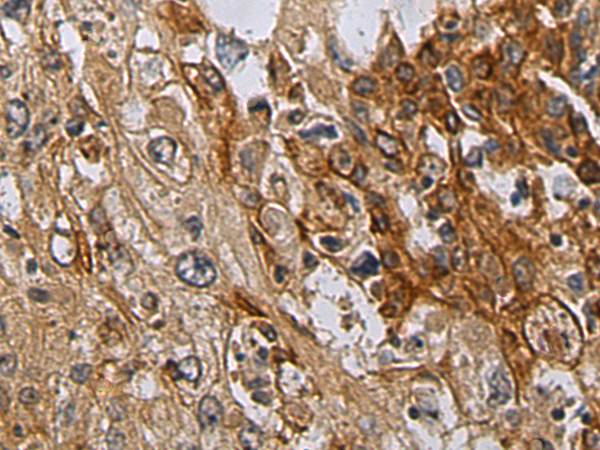

IHC positive control: |

Human liver cancer |

IHC Recommend dilution: |

100-300 |